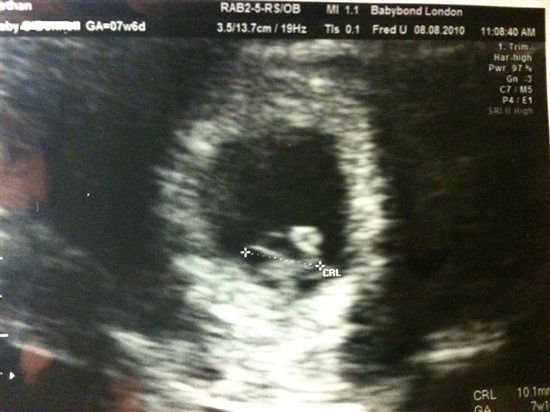

I uploaded a photo in the discussion of bethanw

Hi girls! Yesterday I had an early pregnancy scan. Basically the grey horizontal mass with the measurement across it is the baby. The white circle above, which looks a bit like a speech bubble, is what will be the placenta. I know it's not much but...